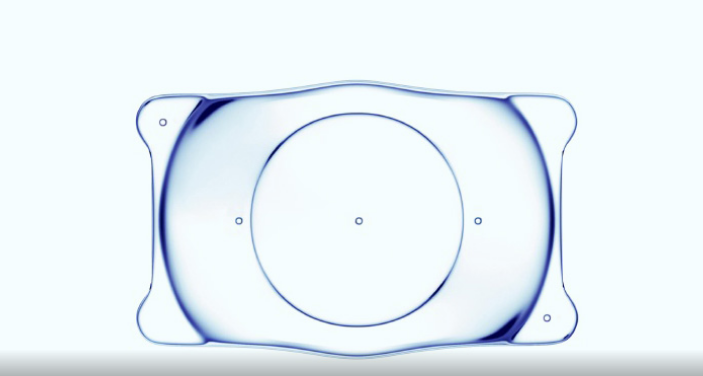

ICL晶体植入只需一个为放置ICL通过的切口大约2mm,不切削损耗角膜,对角膜厚度无要求。具有可逆性,可取出。

ICL晶体材料是一种特殊的胶原共聚物,生物相容性特别高,结构柔软且富有弹性。

厚度仅50微米左右,可轻松植入眼睛内(不会造成眼睛内部的反应)不会引发干眼症很稳定。

适用范围广,中、低度不想切削角膜患者,高度、超高度近视患者都可选择。

独有的材料还提供了紫外线防护功能,且不影响正常的视觉效果。